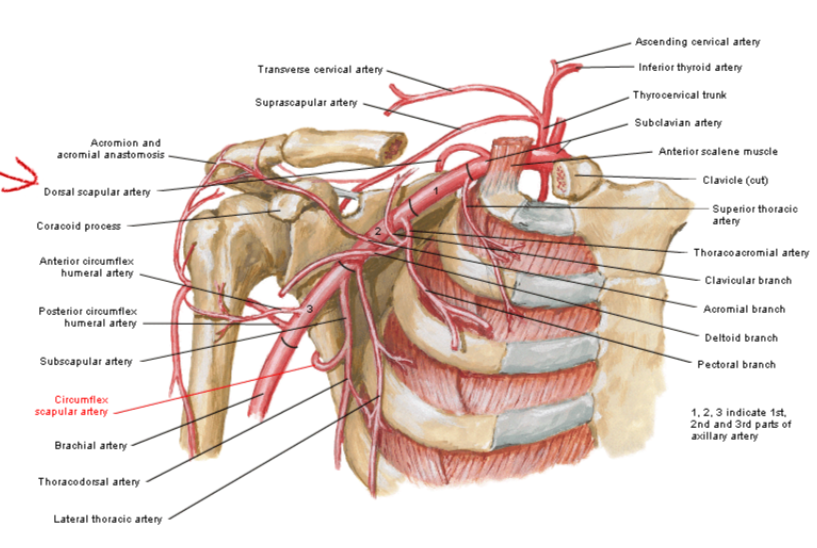

Subclavian a.

Scalene m.

ant.,mid. scalene insertion at rib 1

post. scalene insertion at rib 2

Thyrocervical trunk

Axillary a.

- suprascapular a. (>80%)

subclavian vein 在ant. scalene m. 上方